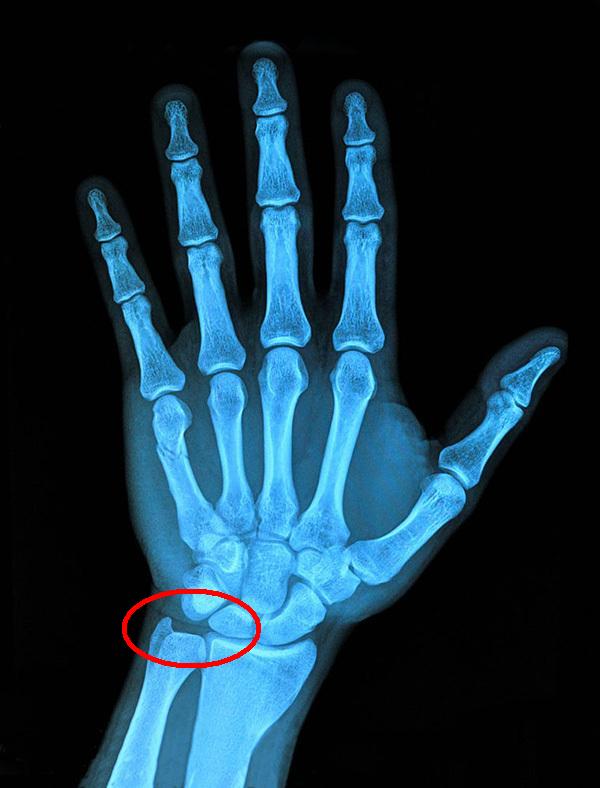

从腕关节受伤的具体部位来说,主要分为大拇指一侧的腕管综合征、桡骨茎突腱鞘炎,小拇指一侧的三角盘软骨损伤三种。

1.腕管综合征,俗称鼠标手,一般为慢性损伤。病因是因为正中神经在腕管内遭到挤压而引起的一种周围神经卡压综合征,主要表现为腕前部疼痛、手部麻木无力,常见于拇指、食指、中指。

健身过程中导致腕管综合征的主要原因是腕关节受到过度压迫,其次是腕关节周围出现骨折、脱位或畸形,治愈后腕管管腔变小,压迫神经;腕管内腱鞘囊肿等疾病使腕管内容物增多而挤压神经;职业因素过度使用手腕等。中轻度可保守治疗,严重则需要手术治疗。

2.桡骨茎突腱鞘炎,一般为慢性损伤。主要是因为反复活动手腕和大拇指,导致拇长展肌和揖短伸肌反复扭转或受伤后腱鞘发生炎症和水肿。主要表现在桡骨茎突处隆起、疼痛,可向前臂及拇指放射痛,活动腕及拇指时疼痛加重,不能提重物,握拳、握杯或拧螺丝时有明显疼痛感。多数情况下经局部封闭等治疗即可,不需要使用其它药物,个别患者需要手术治疗即可。腱鞘炎也可能发生在腕关节和手掌的其它部位。

3.三角盘软骨损伤,一般为慢性损伤,也有急性损伤的可能。损伤的主要原因是腕关节的三角盘软骨处反复受到大重量挤压和拉伸、腕关节反复弯折和弯折时受力不均。症状较轻时可保守治疗,严重时需要手术治疗。